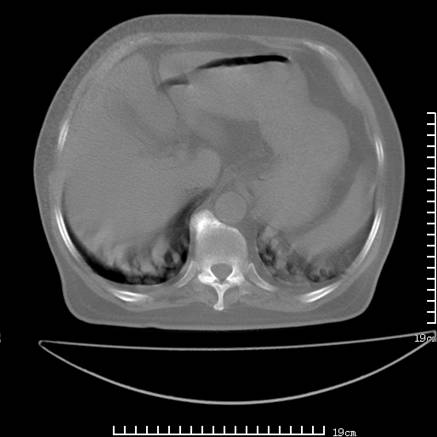

张男,75岁,干咳半年余,小便不利二年,b超检查前列腺增大,未见明显肿块;前列腺癌血生化检查多项指标明显增高。

双肺内多发转移瘤,纵膈淋巴结转移。来源前列腺?建议盆腔mri进一步检查。